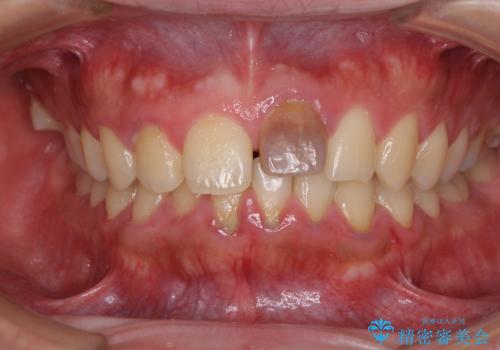

- 中学生の時にぶつけて以来、そのままにしていたところ前歯が変色してきたとのことで来院された患者様です。

レントゲン写真より、歯の中の神経組織が失活していることが分かったため、根管治療、ファイバーコアによる土台築製を行い、オーダーメイドタイプのオールセラミッククラウンにて補綴することとしました。